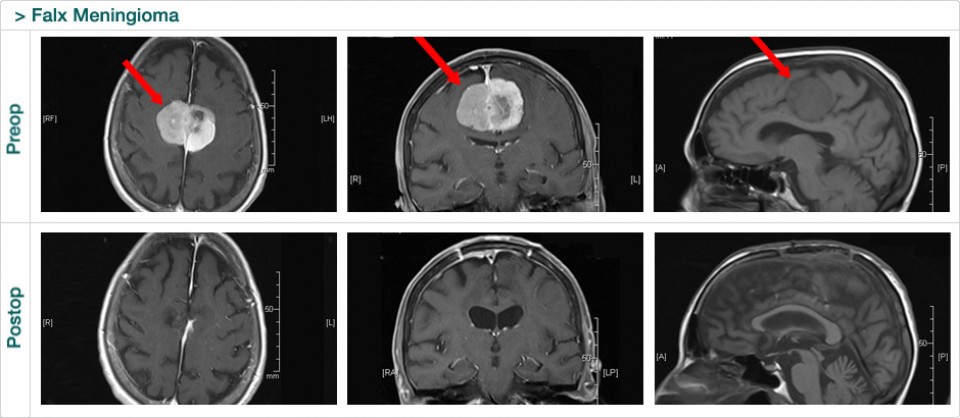

Dr. Attia is an attending neurosurgeon and the director of skull base surgery service in the department of neurosurgery at Sheba Medical Center in Tel HaShomer. His specialty focuses on skull base and cerebrovascular neurosurgery.